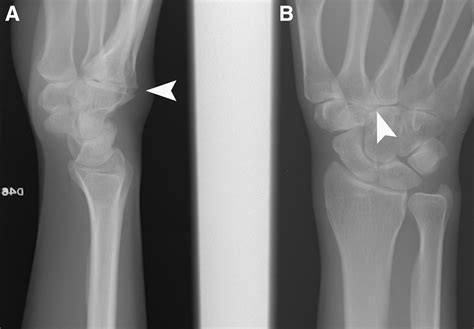

• X-ray Imaging: This is the gold standard for confirmation. An X-ray will clearly show the bony overgrowth at the CMC joints, distinguishing it from a soft-tissue cyst.

• carpal boss x ray